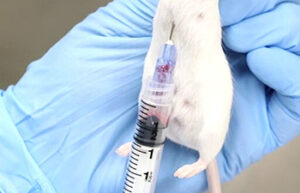

- Blood sampling from the heart, tail vein, jugular vein and ocular sinus

- Animal injections: subcutaneous, intramuscular, intravenous and peritoneal